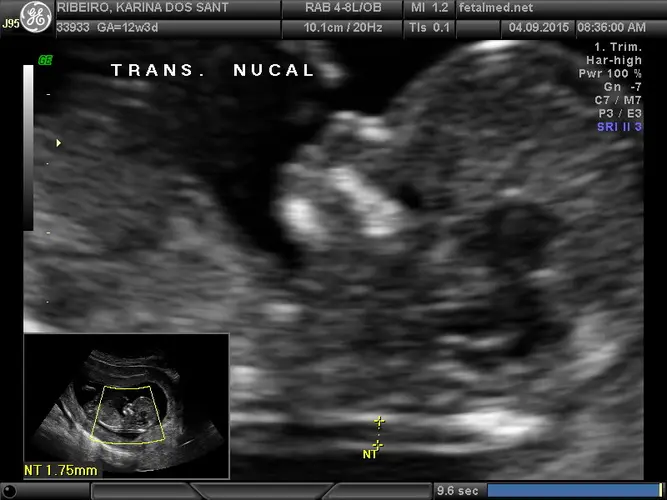

Você sabia? Esta é a época ideal para realizar o morfológico de primeiro trimestre, que inclui a medida da translucência nucal. Este exame ajuda na avaliação de possíveis alterações cromossômicas, como a síndrome de Down.

A 12ª semana é considerada o período ideal para a realização do morfológico de primeiro trimestre, também conhecido como ultrassom de translucência nucal. Este exame é fundamental para avaliar o risco de alterações cromossômicas, especialmente a síndrome de Down.

Durante este ultrassom, o médico irá medir a translucência nucal (um pequeno acúmulo de líquido na região da nuca do bebê), verificar a presença do osso nasal e avaliar o fluxo sanguíneo através do ducto venoso. Estas medidas, combinadas com sua idade e exames de sangue, fornecem uma estimativa personalizada de risco.